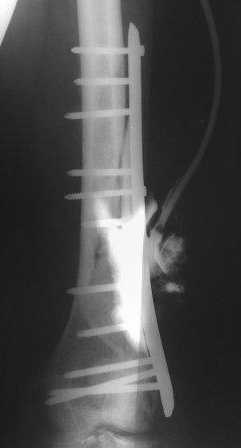

Пациент 25 лет, после автоаварии - переломы обоих бедер и обеих голеней. Поэтапно произведен накостный остеосинтез всех сегментов( все переломы внутрисуставные в\3 голеней и н\3 бедер)Левое бедро после остеосинтеза пластиной нагноилось. Дважды производилась открытая санация с последующим дренированием. Сейчас рана 10 х 3см с гнойным отделяемым. Есть мысль убрать пластину, санировать рану, убрать секвестры, фиксировать в АВФ. А как вы думаете?

Очень интересно - похоже остеосинтез проведен блокированной пластиной, вообще не видно кортикальных винтов. Необходимо данные по срокам с момента травмы и остеосинтеза,необходима вторая проекция. Какой перелом - открытый или закрытый? Обширность повреждения мягких тканей? ДЛя определения тактики лечения много дополнительной входядей информации необходимо, если возможно вид раны. Теоретически При надежности остеосинтеза блокированной пластиной и качественной пластине можно её оставить, аппарат не добавит удобств. удалить секвестры и дренировать. Удалить часть винтов в середине пластины где секвестры, чтобы проявились эластические свойства пластины для стимуляции остеогенеза, у 25 летнего возможен спонтанный регенерат. Но все это по ходу лечения в зависимости от динамики и течения процесса лечения, поведения пациента. Подумайте может быть если у Вас нет опыта лечения столь сложного пациента лучше отдать его в специализированную клинику. Срок полного лечения и восстановления может занять несколько лет. Но если вопрос только в аппарате то можно и в аппарате, но для больного это будет достаточно мучительно.

Спасибо большое, коллеги. Дополню. С момента травмы прошло 5 месяцев. Пластина действительно блокированная. Пациент, конечно истощен, самостоятельно перемещаться не может. Рана после ревизии 10х3см по краям гранулирует. На дне раны немного гнойного отделяемого. фото раны представлю чуть позже. А пока добавляю боковую и 3\4 проекции.:

С момента травмы прошло 5 месяцев. Пластина действительно блокированная. Пациент, конечно истощен, самостоятельно перемещаться не может. Рана после ревизии 10х3см по краям гранулирует. На дне раны немного гнойного отделяемого. фото раны представлю чуть позже. А пока добавляю боковую и 3\4 проекции.: